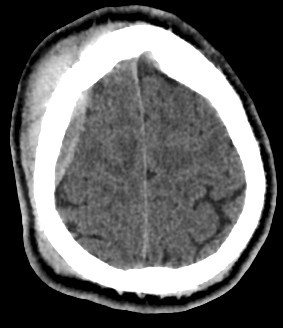

• A well-defined extraxial elliptical shape fresh blood density seen in the right fronto-parietal region.

• The lesion exert little mass effect in the form of effacement of the cortical sulci and and mild midline shift.

• right fronto parietal subglial hematoma seen

acute extradural hematoma with fracture

• Biconvex (lentiform) hyperdense collection adjacent to the inner table of the skull.

• Does not cross sutures (limited by dural attachments).

• Mass effect: midline shift, compression of adjacent sulci or ventricles.